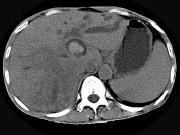

问题 男,44岁,右上腹痛半年,腹部未触及包块,轻度黄疸,AFP阴性,CT检查如图,最可能的诊断为()

选项 A.原发性肝癌 B.胆管细胞癌 C.肝囊肿 D.肝脓肿 E.肝血管瘤

答案 B